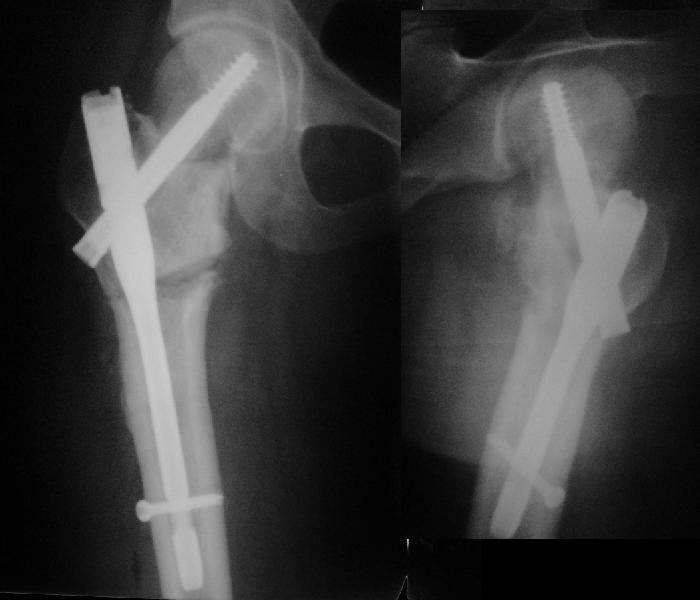

Я бы ограничился вальгизацией без вмешательства в зону перелома шейки. Биология здесь, надо полагать, хорошая, необходимо только улучшить механическую составляющую.

В итоге что-то такое и сделали. Убрали DHS, остеотомия, синтезировали Affixus с небольшой вальгизацией. Снимки в приложении.